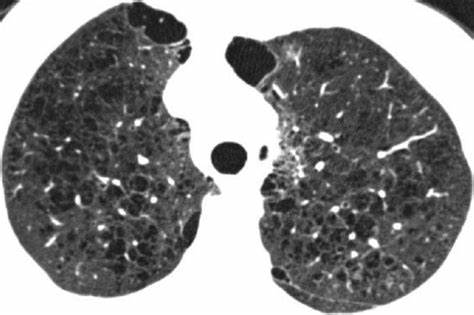

- CT scan

- Restrictive lung disease